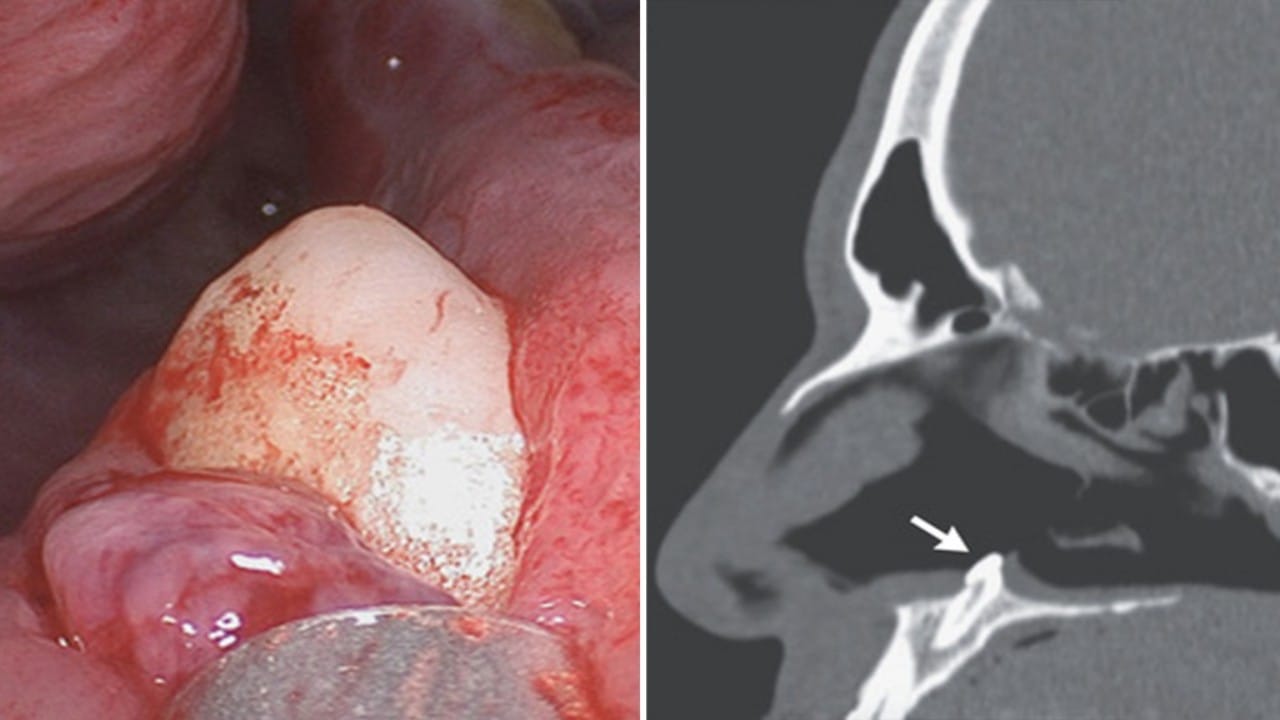

رجل يعاني من صعوبة التنفس بسبب نمو سن داخل أنفه

منذ 3 سنة

0

1642